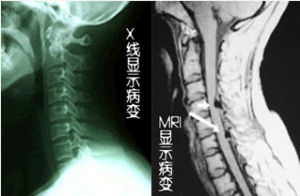

頸椎管狹窄症X線平片檢查頸椎發育性椎管狹窄主要表現為頸椎管矢狀徑減少。因此,在標準側位片行椎管矢狀徑測量是確立診斷的準確而簡便的方法。椎管矢狀徑為椎體後緣至棘突基底線的最短距離。凡矢狀徑絕對值小於12mm,屬發育性頸椎管狹窄、絕對值小於10mm者,屬於絕對狹窄。用比率法表示更為準確,因椎管與椎體的正中矢狀面在同一解剖平面,其放大率相同,可排除放大率的影響。正常椎管/椎體比率為1∶1,當比率小於0.82∶1時提示椎管狹窄,當比率小於0.75∶1時可確診,此時可出現下關節突背側皮質緣接近棘突基底線的情況。

3.MRI檢查

MRI可準確顯示頸椎管狹窄的部位及程度,並能縱向直接顯示硬膜囊及脊髓的受壓情況,尤其當椎管嚴重狹窄致蛛網膜下腔完全梗阻時,能清楚顯示梗阻病變頭、尾側的位置。